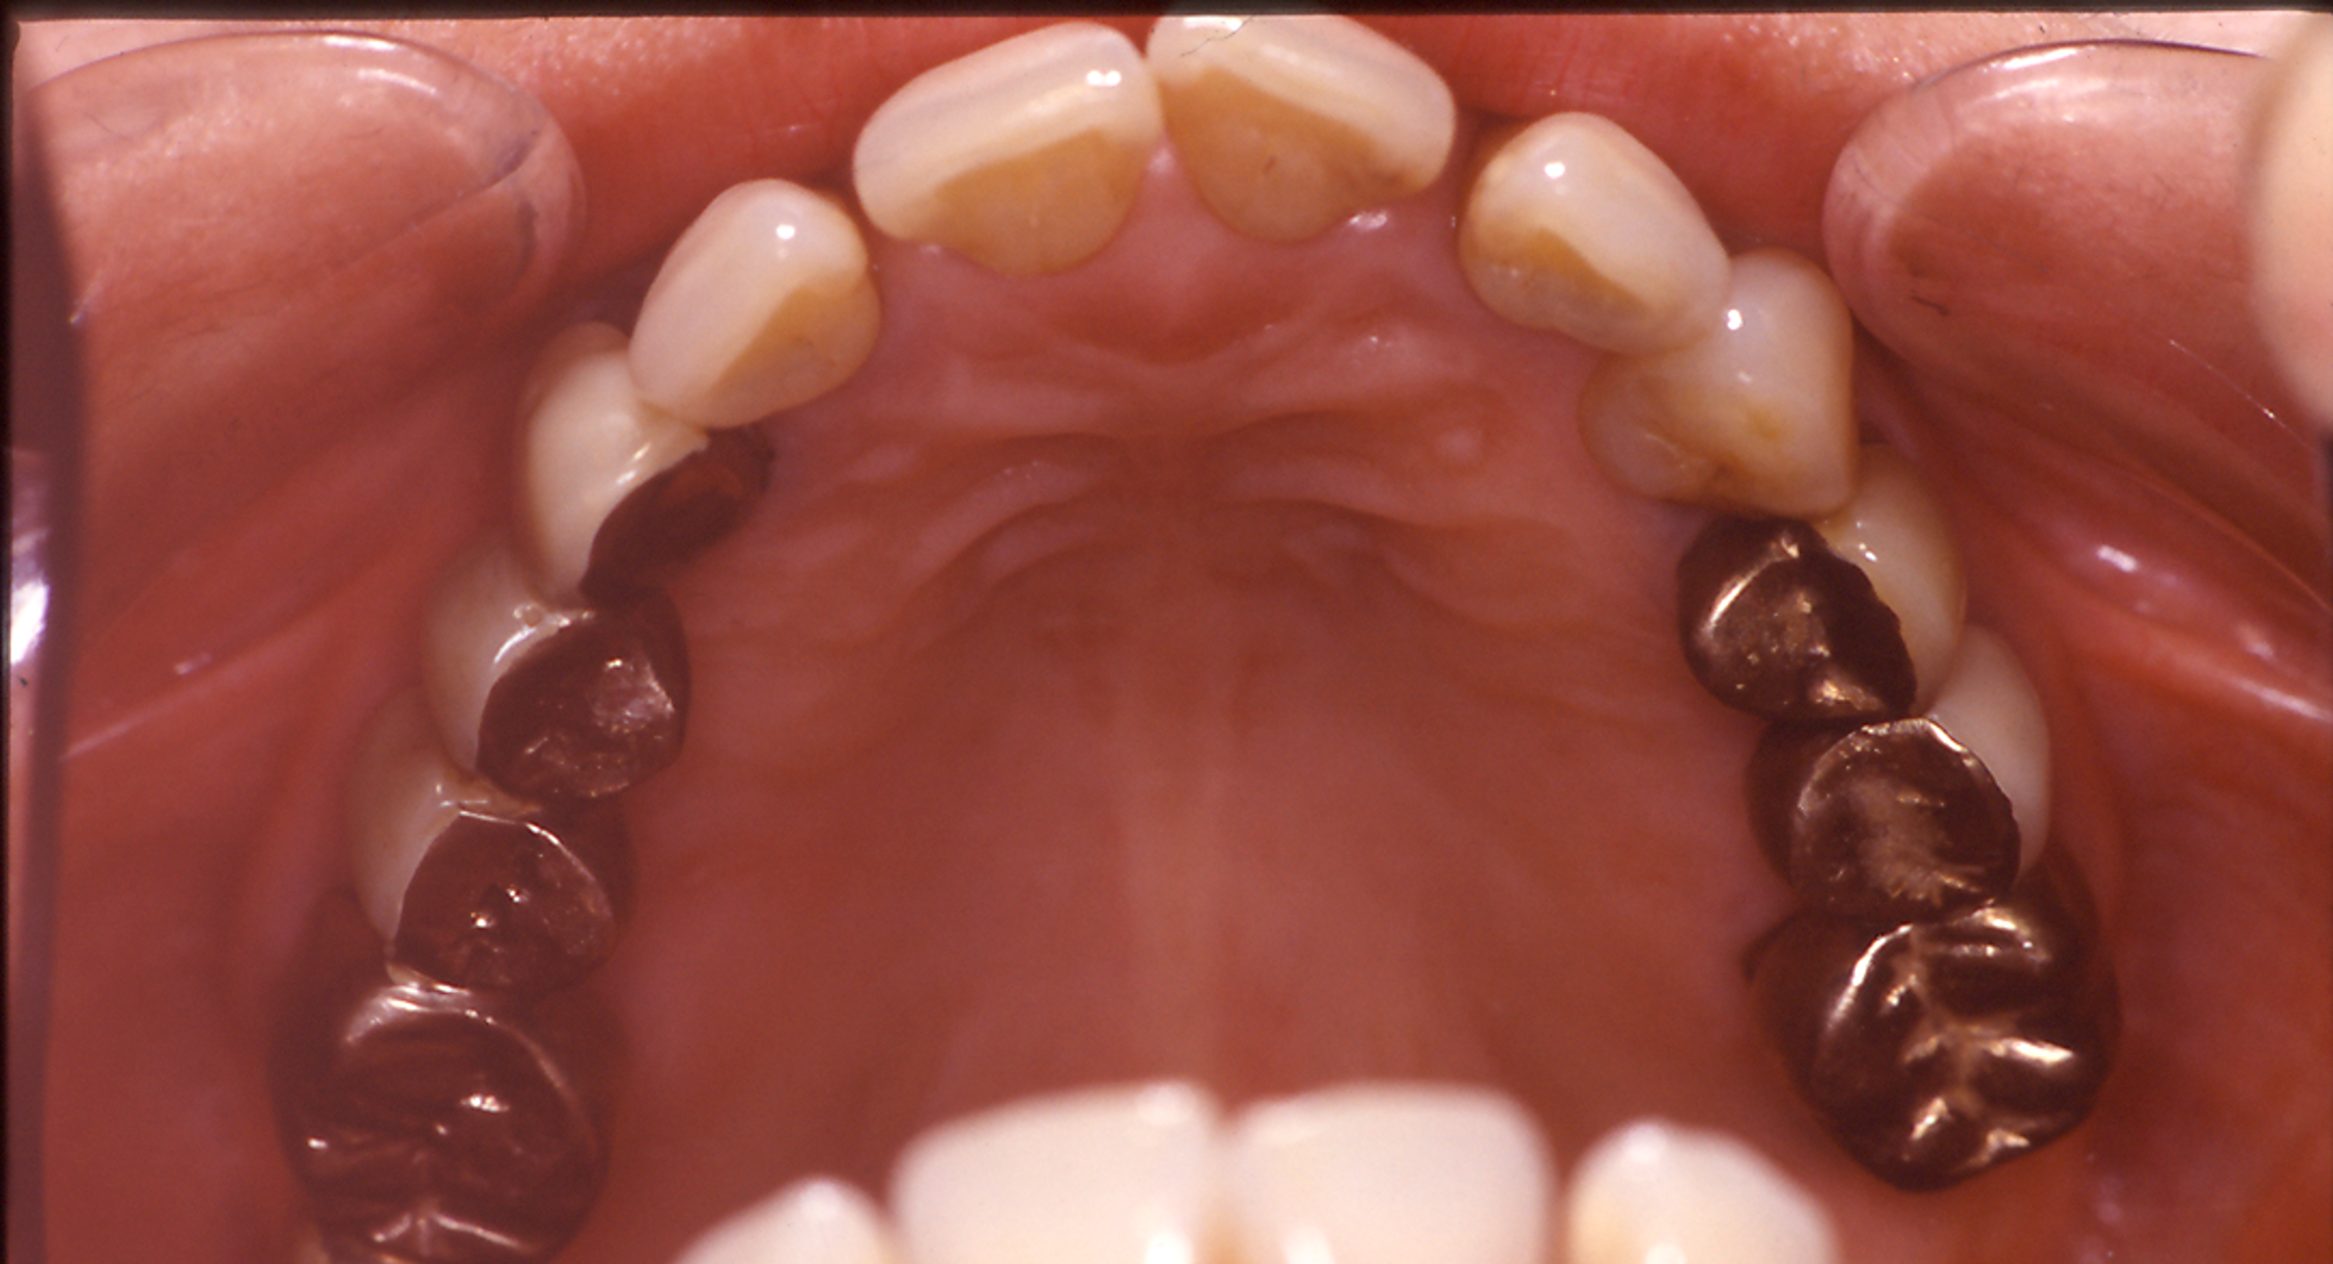

拝見したところ、右下奥歯4本(第1小臼歯/4番、第2小臼歯/5番、第1大臼歯/6番、第2大臼歯/7番)は歯がない「欠損」の状態で、入れ歯が装着されていました。

本来なら全て抜歯をして総入れ歯やインプラントにしなければいけないほど重度の歯周病でした。

まず初めに、元々装着されているブリッジを除去して仮歯に置き換え、上前歯にはワイヤーを貼り付けて固定しました。

次に歯周病の治療を行い、歯茎の状態の改善を図りました。

その後、残っている歯に内冠を装着し、パラレロコーンスコープデンチャーを作製しました。